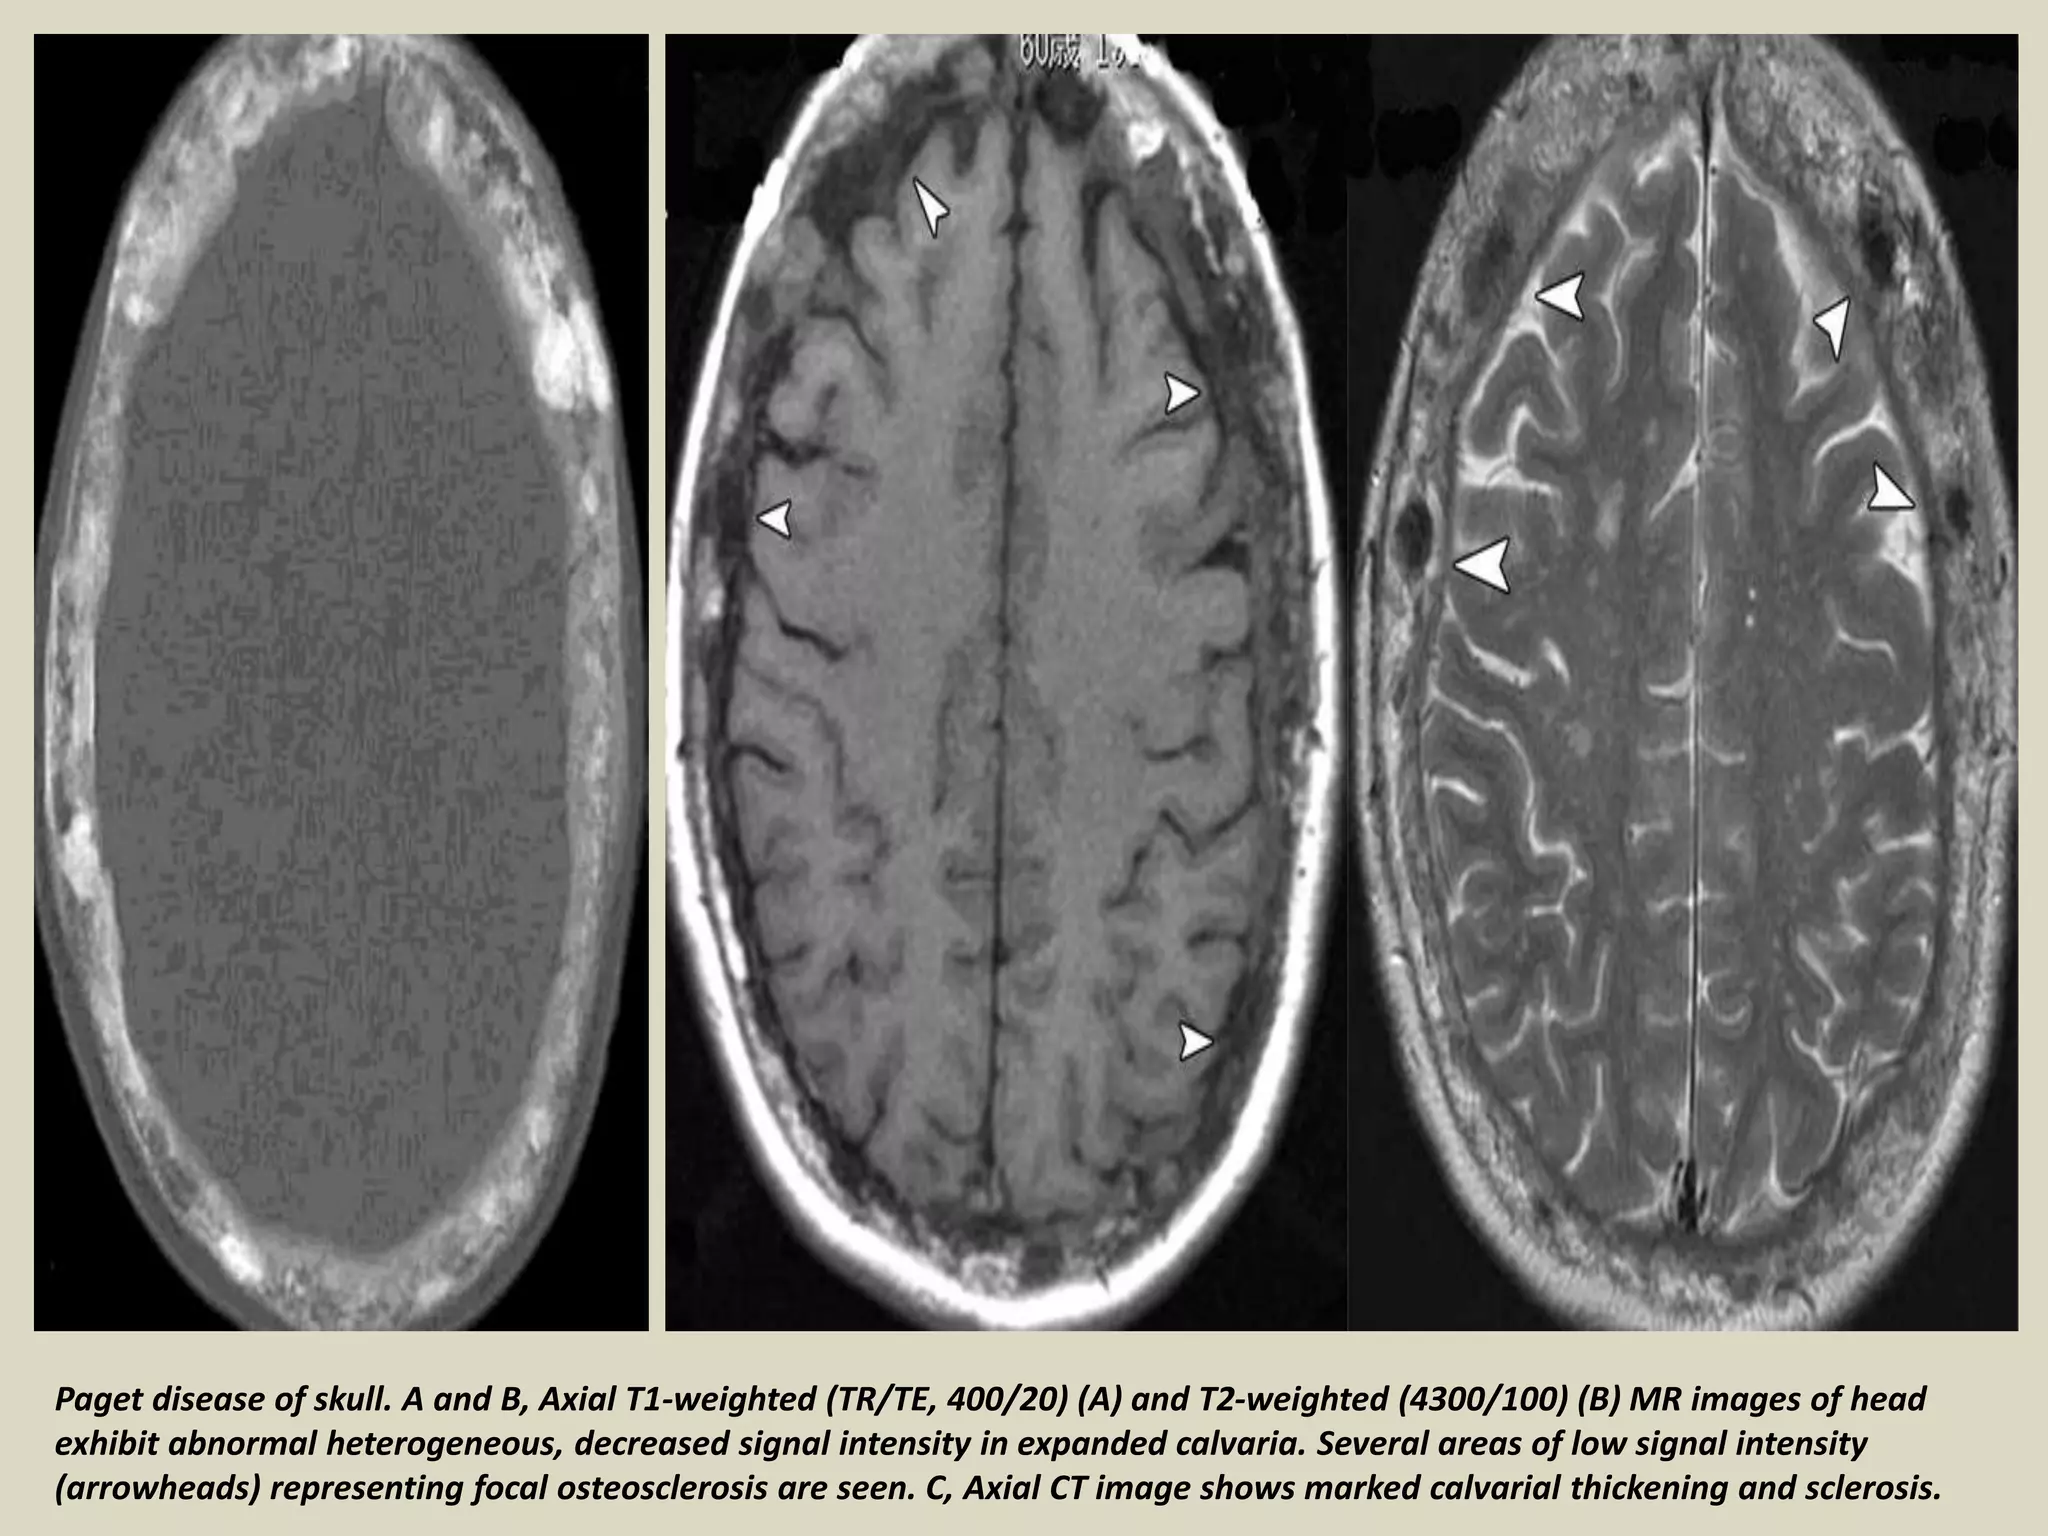

Paget disease of skull. A and B, Axial T1-weighted (TR/TE, 400/20) (A) and T2-weighted (4300/100) (B) MR images of head

exhibit abnormal heterogeneous, decreased signal intensity in expanded calvaria. Several areas of low signal intensity

(arrowheads) representing focal osteosclerosis are seen. C, Axial CT image shows marked calvarial thickening and sclerosis.

Paget disease ofskull. A and B, Axial T1-weighted (TR/TE, 400/20) (A) and T2-weighted (4300/100) (B) MR images of head exhibit abnormal heterogeneous, decreased signal intensity in expanded calvaria. Several areas of low signal intensity (arrowheads) representing focal osteosclerosis are seen. C, Axial CT image shows marked calvarial thickening and sclerosis.